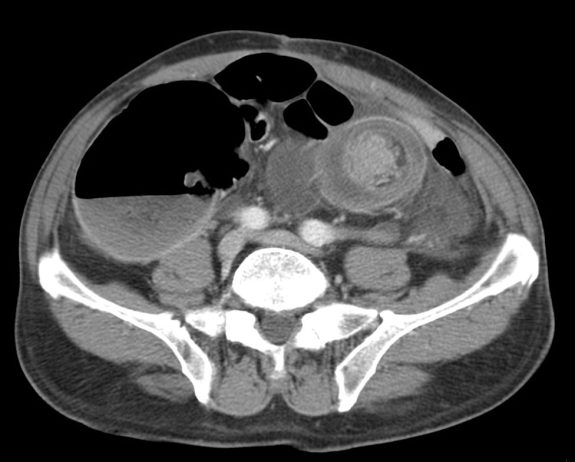

Tomografía Computarizada:

Con sensibilidad y especificidad próximas al 100%, es la técnica inicial de elección ante la sospecha de una obstruccion intestinal. Ante la sospecha firme de obstruccion intestinal, realiza un diagnóstico más preciso, aporta más información adicional y evita retrasos en el diagnóstico.

Hallazgos:

- Distensión proximal a la obstrucción mayor de 3,5 cm en el intestino delgado y mayor de 5 cm en el colon con colapso de asas distales junto con la identificación, siempre que sea posible, de la zona del cambio de calibre (zona de transición), lo que nos permite realizar con mayor seguridad el diagnóstico.

- Si se observan asas dilatadas, independientemente del grado, si no hay colapso de asas distales, el diagnóstico más probable es un íleo paralítico.

- Nivel de la obstrucción: determinado por la zona de cambio de calibre.

Tomografía computarizada: S y E del 93% y 100% respectivamente. Hallazgos: Dilatación por obstrucción de asas de delgado. Aerobilia. Litiasis (2 – 3 cm aprox). Hay que tener cuidado ya que muchas litiasis no están calcificadas y su densidad puede ser similar al contenido del intestino. Pueden ser multiples, por tanto hay que poner atención para que no pasen desapercibidas y evitar las recidivas. Fistulas (normalmente entre vesícula y duodeno). Neumoperitoneo (gas portal o gas mural indican peor pronóstico).